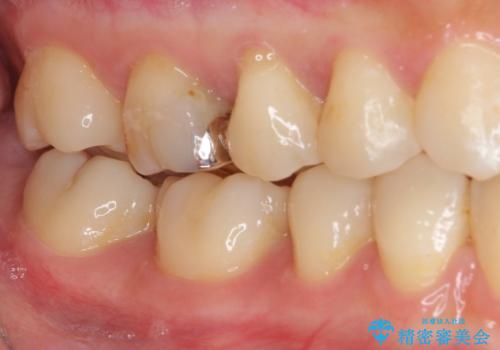

セラミックインレーを装着したことで、とても自然な仕上がりとなりました。

患者様も大きく口を開けても気にならなくなった、大変喜んでくださいました。